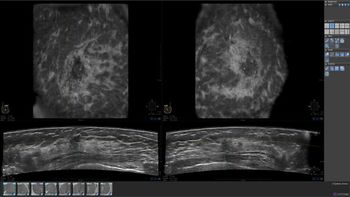

Why hasn’t breast ultrasound screening been incorporated into routine clinical practice? In this second part of a series, I examine real and perceived barriers to screening with ABUS, including clinical and technical workflow, training, and density notification.

With demonstrated value as an adjunct to screening mammography, I believe ABUS can be the modality that improves screening for women with dense breasts. I believe ABUS can be used to reduce interval cancers in women with dense breast tissue now being missed by relying on screening mammography only.